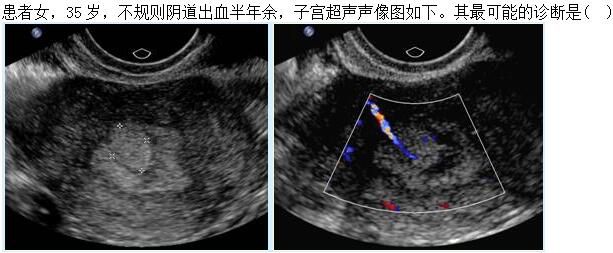

A.子宫黏膜下肌瘤

B.子宫内膜息肉

C.子宫内膜不典型增生

D.子宫内膜癌

E.子宫绒毛膜癌